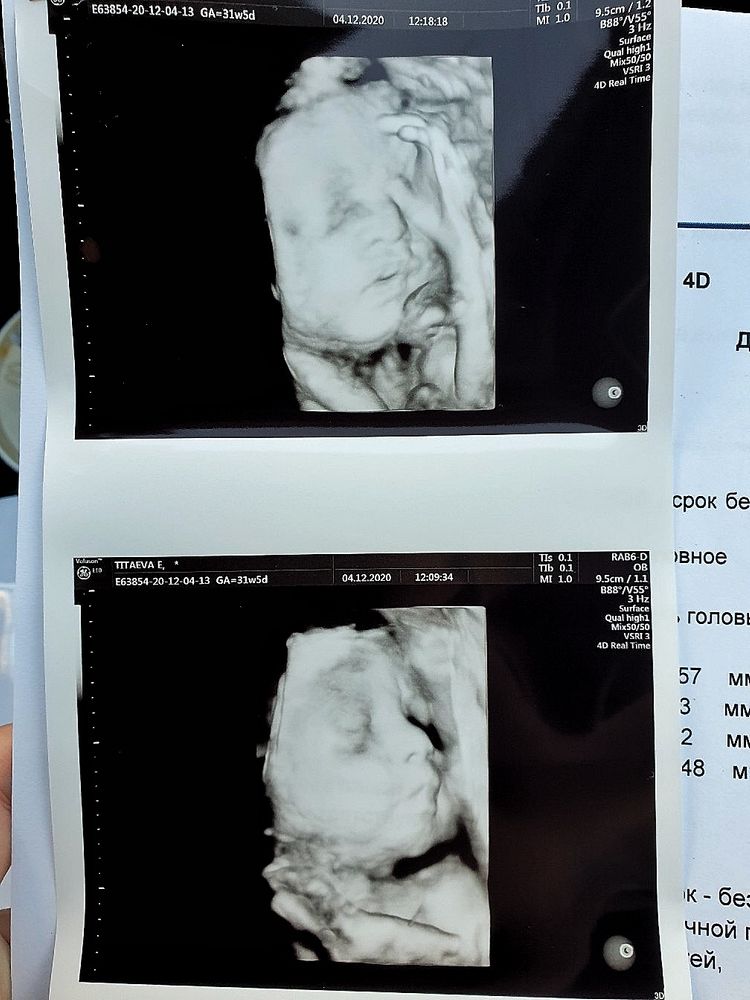

Trinnity, нет, все делала в 3д в платной клинике. Вот, кстати, какие они в 20 и 30 недель 😄 Изображение Изображение

Весь осмотр был в 2д, но несколько раз включали 3д для фото. Фото распечатали (их много). В формате 3д видео, в своем случае, ничего толкового не увидела. Плацента сливалась с лицом и все ооочень приблизительно. 2д видео для меня было понятнее. А на 3д фото один в один изображение младенца, врач сделала чётче некуда (на сроке 25н).